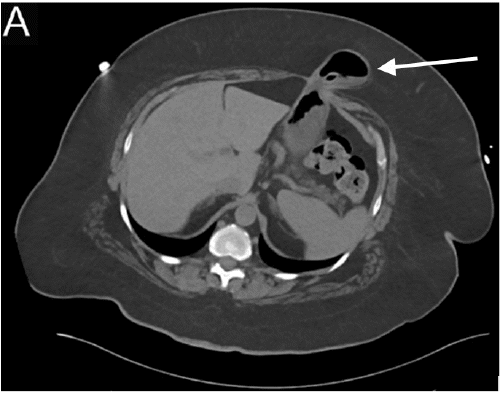

A computed tomography (CT) scan of the abdomen and pelvis revealed gastric herniation through a fascial defect associated with her gastrostomy tube (Figure 1). The stomach had no signs of stranding or ischemia to suggest strangulation, and there was no evidence of surrounding soft tissue edema.

Figure 1. CT Abdomen Without Contrast. Published with Permission

A) Axial slices demonstrating gastric hernia (arrow); the gastrostomy tube is visualized

B) Sagittal view demonstrating gastric hernia (arrow)